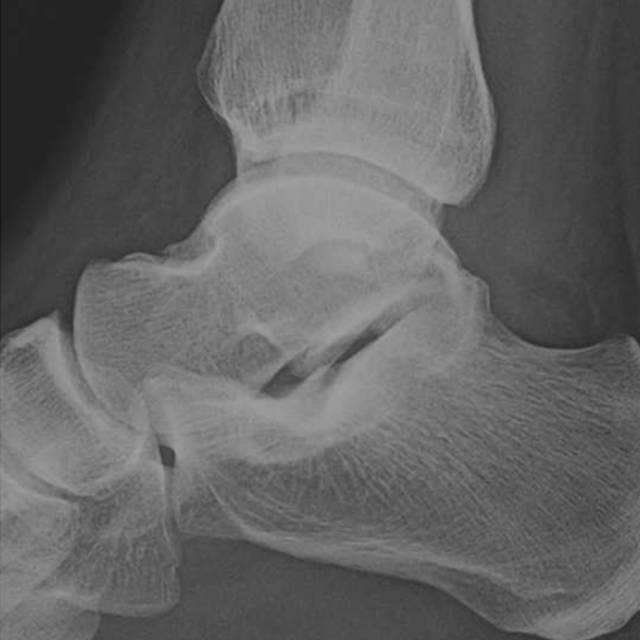

在脚踝处,必须警惕超出投照视野(图4)的足部腓骨骨折的可能性和足部骨折的可能性。例如,Maisonneuve骨折是一种旋前 - 旋转损伤,伴有远端胫腓骨间继位断裂和近端腓骨骨折[19]。了解骨折模式与相关的损伤机制模式至关重要,特别是在踝关节[20]。

图。4A-28岁女子在地面跌倒后。A,踝关节的斜视图显示继发性加宽和微小的内侧踝撕裂性骨折。B,近侧腿的侧视图显示倾斜的近端腓骨骨折,构成Maisonneuve骨折。